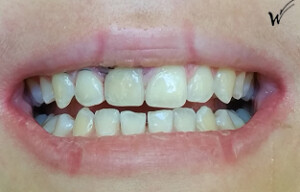

Cas clinique « SMILE RED FLAG MEI » : Traitement de remplacement d’une dent du sourire par un implant en Mise en Esthétique Immédiate. Visualisation de la version définitve de la couronne sur implant avec un cosmétique en céramique.

Après la guérison des tissus mous (gencive) et durs (os alvéolaire), la couronne céramique esthétique a été installée sur l’implant.

Le maintien de l’esthétique du sourire dépend en grande partie de la reconstruction des tissus gingivaux entourant la couronne céramique esthétique et de l’os autour de l’implant.